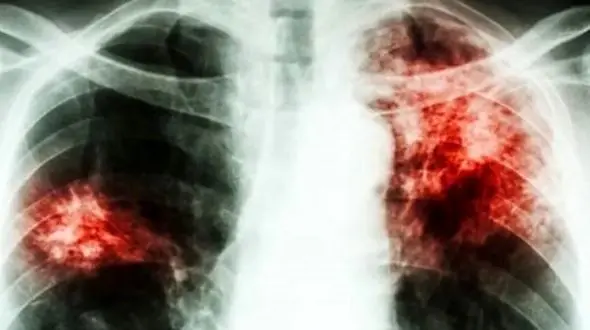

رکنا: بیماری سل همچنان مرگبارترین بیماری عفونی جهان است و در سال 2024 جان 1.23 میلیون نفر را گرفت؛ با وجود کاهش جزئی موارد ابتلا و مرگومیر، کمبود بودجه و نابرابری همچنان تهدیدی جدی برای مهار آن است.

رکنا: سازمان جهانی بهداشت (WHO) روز گذشته (سهشنبه) دادههای هشداردهندهای منتشر کرد که نشان میدهد سل (TB) بار دیگر به عنوان کشندهترین بیماری عفونی جهان رتبهبندی میشود.